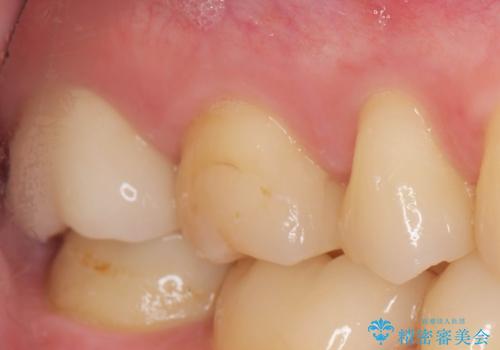

天然歯と変わらない色調に優れるセラミック治療の仕上がりに満足いただくことができました。

- 20.9万円(ジルコニアクラウン・仮歯・セラミックインレー)費用は治療当時の料金となります